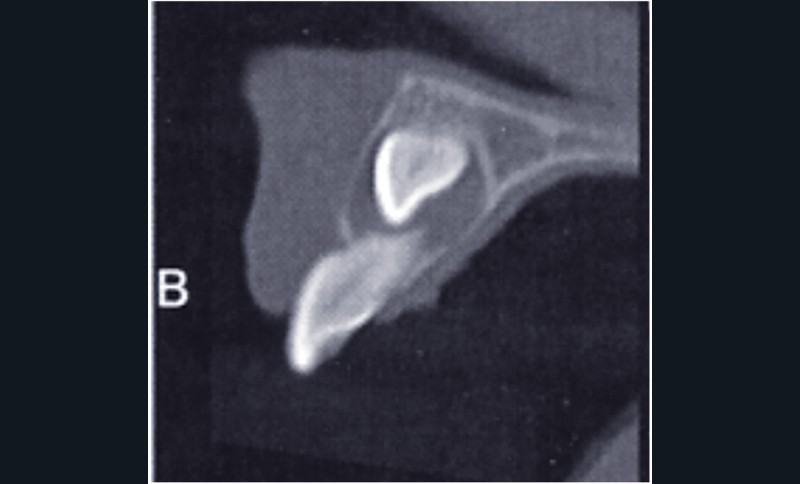

On observe un kyste péricoronaire sur 23 (fig. 2a).

La couronne de 23 est haute et discrètement vestibulaire par rapport à la racine de 21, partiellement résorbée.

La résorption radiculaire de 21 est en relation avec la couche cellulaire épithéliale périphérique du kyste. La présence de ce kyste laisse supposer une progression lente. Le pronostic serait probablement davantage défavorable s’il n’y avait pas de formation kystique autour de la 23.